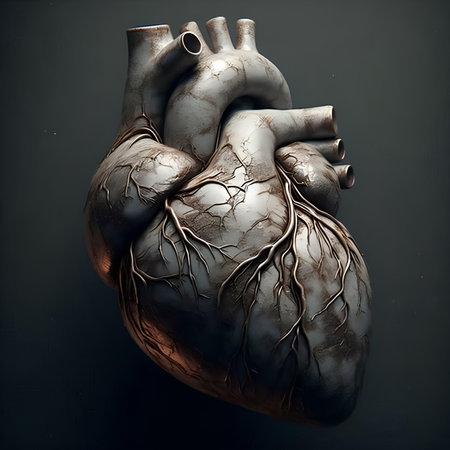

3D рендеринг человеческого сердца с венами на чёрном фоне.

Медицинская 3D иллюстрация человеческого сердца с высокой точностью.